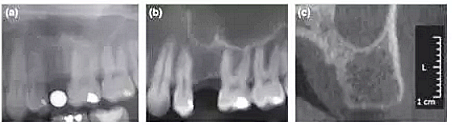

本研究旨在比較數(shù)字化全景片、CBCT重建全景片及CBCT斷面影像在術(shù)前選擇種植體(4種種植體系統(tǒng))尺寸(直徑和長(zhǎng)度)中的應(yīng)用。

本研究共納入71名患者,所有擬種植位點(diǎn)行數(shù)字化全景(D-PAN)及錐束CT(CBCT)檢查。攝全景片時(shí),將一直徑5 mm的金屬球置于缺牙區(qū)。重組CBCT數(shù)據(jù)組分別構(gòu)建10 mm層厚的CBCT全景圖像(CBCT-pan)及1 mm層厚的斷面影像(CBCT-cross)。三名測(cè)量者在顯示器上應(yīng)用專(zhuān)業(yè)軟件測(cè)量圖像,在擬種植位點(diǎn)放置4個(gè)參考點(diǎn)以模擬種植體外形。分析比較根據(jù)3種影像選擇的種植體長(zhǎng)度和直徑的差異。并且針對(duì)每種種植系統(tǒng),比較根據(jù)CBCT-cross與其他2種方式(D-PAN和CBCT-pan)選擇的種植體尺寸。

結(jié)果顯示,根據(jù)CBCT-cross選擇的種植體(3個(gè)觀察者取平均值)比D-PAN和CBCTpan選擇的種植體直徑更小。在前磨牙區(qū)域,D-PAN和CBCT-pan選擇的種植體直徑也有顯著差異。相比D-PAN,CBCT-cross選擇的種植體顯著更短。在前磨牙位點(diǎn),3種測(cè)量方式選擇的種植體長(zhǎng)度無(wú)顯著差異。CBCT-cross選擇的種植體尺寸級(jí)別相比D-PAN和CBCT-pan無(wú)顯著差異。

總結(jié)來(lái)說(shuō),本研究的結(jié)果表明利用CBCT重建全景片與CBCT斷層影像選擇的種植體尺寸存在差異。在大多數(shù)病例中,相比全景片或CBCT重建全景片,根據(jù)CBCT斷層影像測(cè)量并選擇的種植體直徑和長(zhǎng)度均更小。